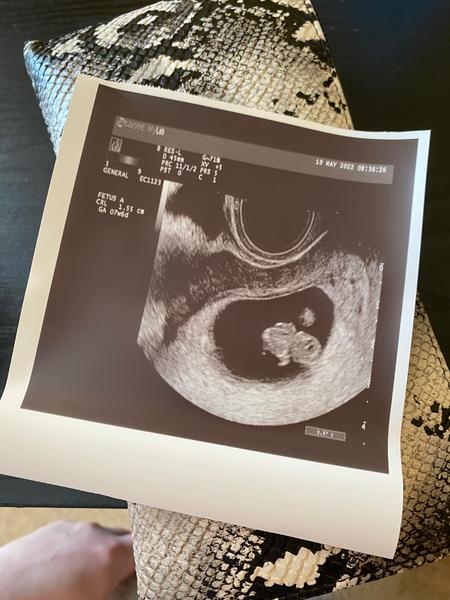

@kvietok2021dt jeeeeeeeeej aj ja chcem take foto mimozemstanka maleho.... Krasne necim nerusene tehulkovanie prajem 🥰🥰🥰

@zuzsat moja prajem nam vsetkym vela zdravia stale to je este malinke a kedykolvek moze odist coz dufam a verim ze nie vcera som uz aj 4 krat vracala :D katastrofa dala mi progestanelle 200mg 2x vecer vkldat nespinim ani nic ale ta pre istotu , verim ze to vsetke dotiahneme do uspesneho konca a verim ze coskoro aj ty budes mat fotku svojho babatka❤️ toto je moje prve tehotenstvo tak je to pre mna vsetko nove.

@kvietok2021dt prve ..tak to je super. Ved pozri. Uz ma 1,5cm maly beťarik. Bude to fajn .. a ten progrstenal je super ze ti dali...

@zuzsat ja neviem to bol uplny zaciatok 6/6 cize 5/6 neviem jak to oni pocitaju :D prvy bol 5.5 a dnes je 19.5 takze ma to sediet .